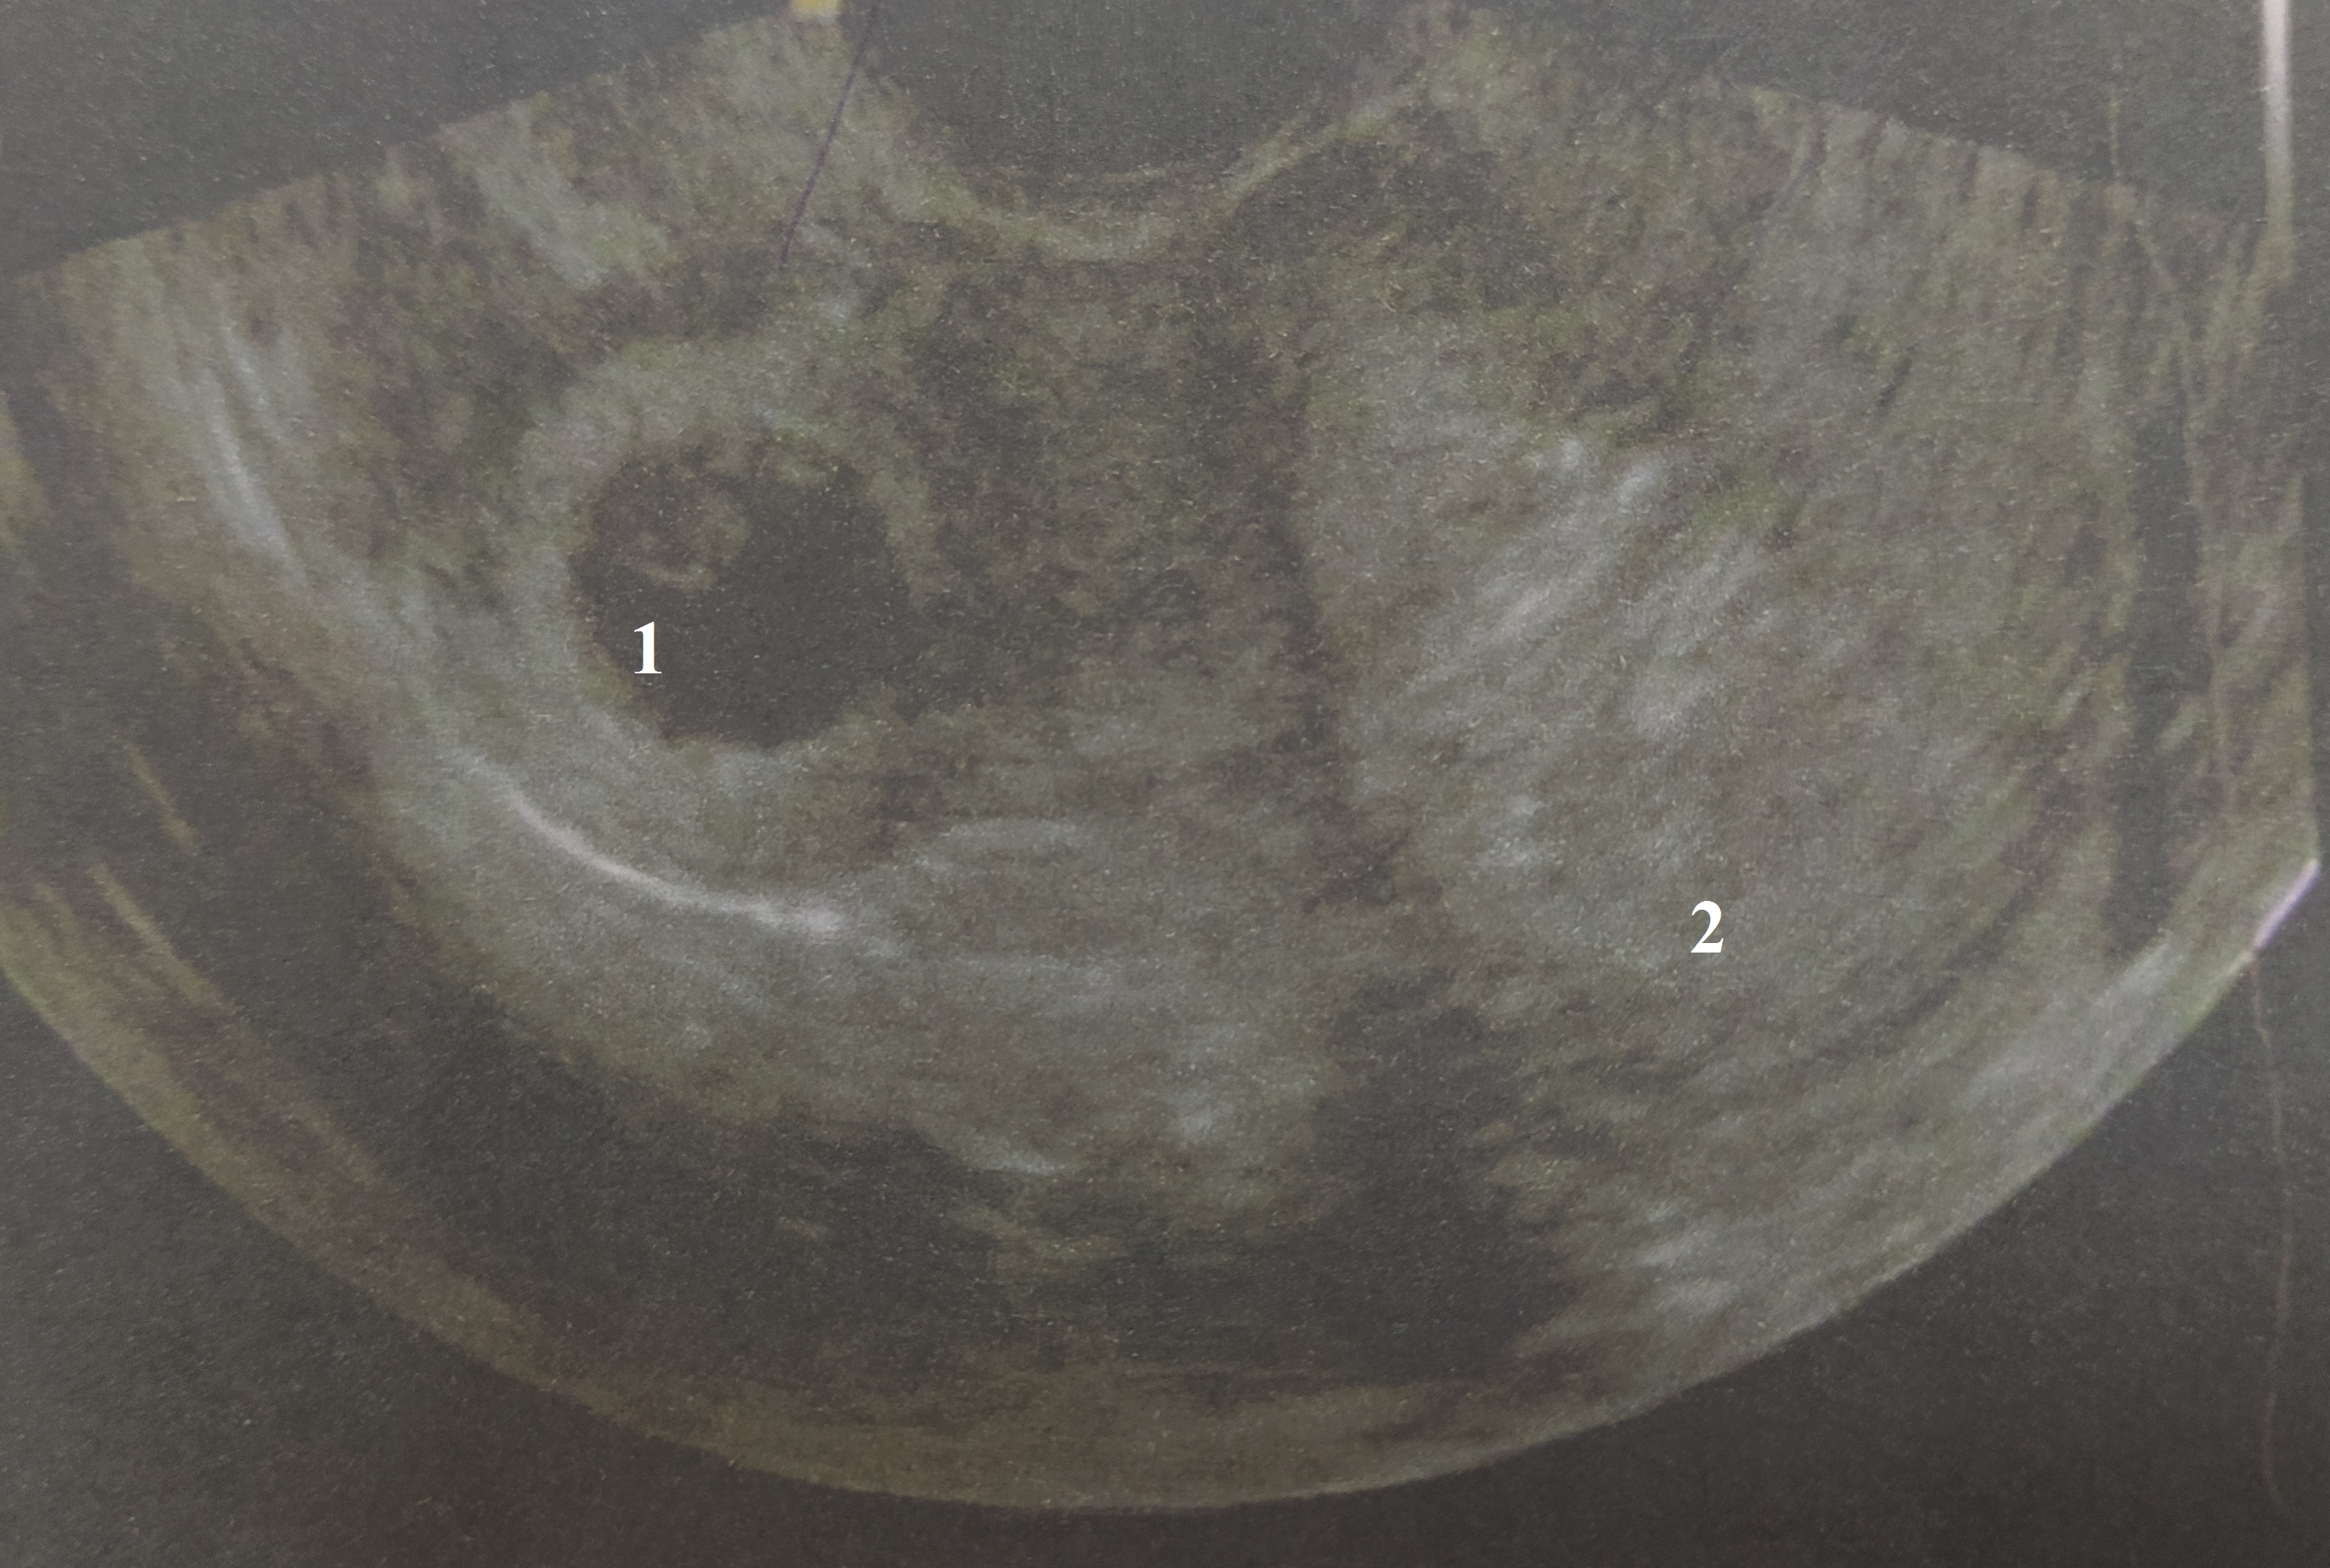

Рисунок 3 - Ультразвуковая сканограмма матки:

1 - полость рога; 2 - полость матки

При трансвагинальном УЗИ (рис.2, рис. 3): шейка 34 мм, эндоцервикс 2,9 мм, однородный. Тело матки 58х47х54мм, эндометрий повышенной эхогенности — 26 мм, с ровными контурами. По правому ребру матки имеется добавочный рудиментарный рог 38х32х35мм, в нем плодный пузырь 17 мм, КТР - 6 мм, сердцебиение определяется, желточный мешок 4,8 мм. Полость рудиментарного рога не сообщается с полостью матки. Яичники: правый 37х22х26 мм с желтым телом 19 мм, левый яичник 32х18х21 мм с фолликулами 5–6мм. Заключение: Беременность 6–7 недель в рудиментарном роге матки.